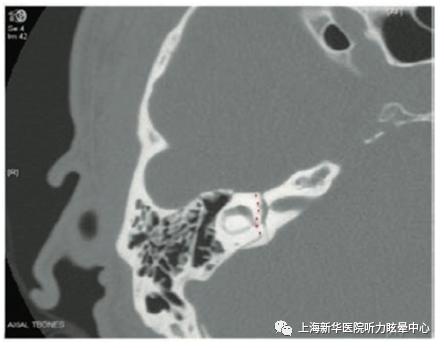

影像学检查:医生可能会建议完善颞骨CT扫描或MRI以确认骨折的位置、类型和严重程度。

三、颞骨骨折的分类基于骨折的解剖路径,以岩部顶部的长轴作为参考,将骨折分为纵向或横向。

1. 纵行骨折 纵行骨折更为常见,占到了70%至90%的骨折。它们沿着外耳道的轨迹进行,顺着岩部顶部的轴线前进,遵循最小阻力的路径。纵行骨折大多是由颞顶区域的冲击引起的。通常伴随着传导性听力下降(CHL),并可能伴有面神经膝状神经节损伤。

2. 横行骨折 横行骨折穿越岩骨嵴,有更高的概率损伤耳囊。这类骨折需要更大的力量,通常是由枕部的冲击引起的。横行骨折更常伴随内耳损伤,导致感音神经性听力下降(SNHL),并有更高的面神经损伤发生率。